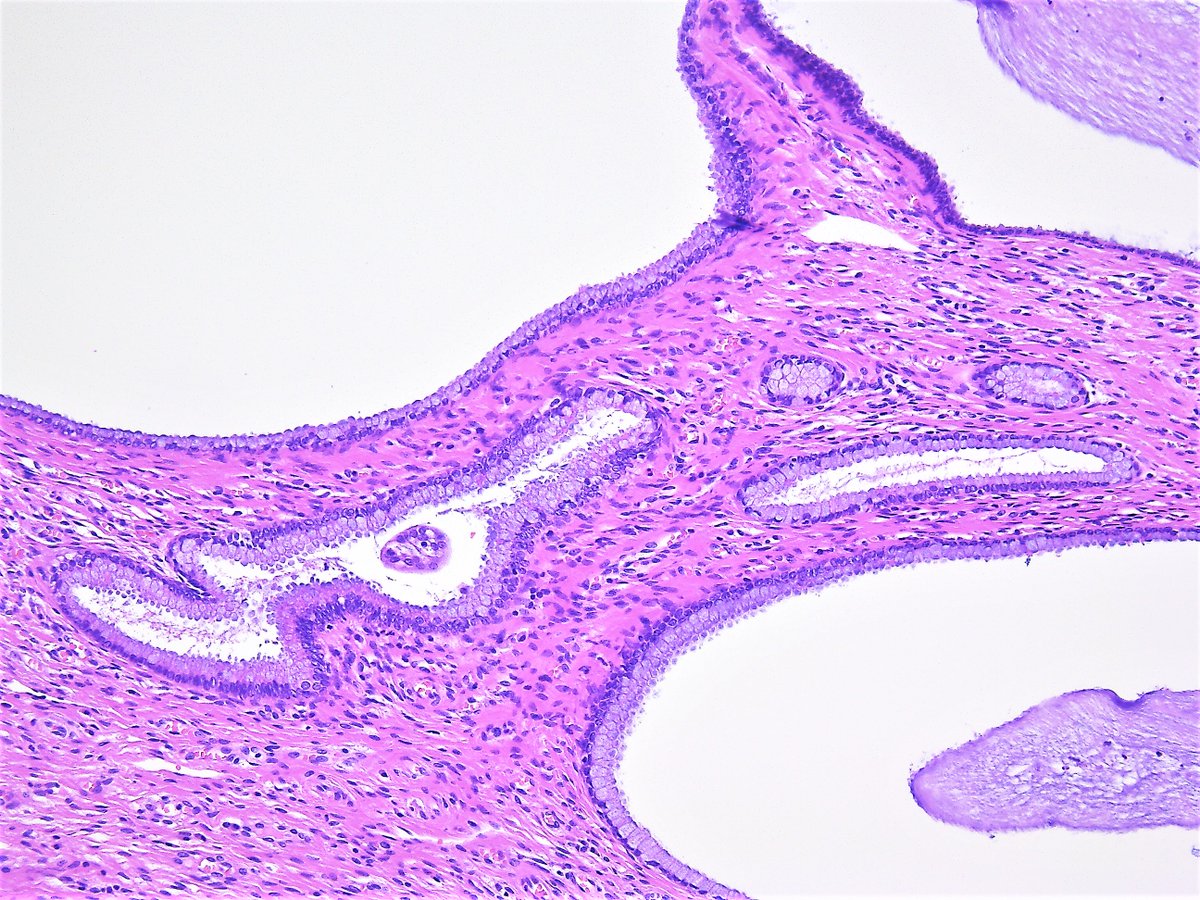

Nabothian cysts also called mucinous retention cysts or epithelial cysts are a common and benign gynecological condition located at the uterine cervix. They are usually asymptomatic of no clinical significance and require no treatment. However if symptomatic or they become complicated further evaluation and therapy are needed.

Pathology Outlines - Nabothian cyst Colloid cysts of the third ventricle are benign epithelial lined cysts with characteristic imaging featuresAlthough usually asymptomatic they can rarely present with acute and profound hydrocephalus. It is a specific type of giant cell in which several epithelioid meaning the cells are big and pink like the cells of the skin macrophages fuse together the nuclei forming a cute horse-shoe shape around the periphery of the cell The topic Cervical Mucinous Retention Cyst you are seeking is a synonym or alternative name or is closely related to the medical condition Nabothian Cyst of Uterine Cervix. Nabothian cysts Squamous metaplasia grows over endocervical glands Mucin gets trapped in glands leading to cystic dilation Nabothian cyst Extremely common of no clinical significance.